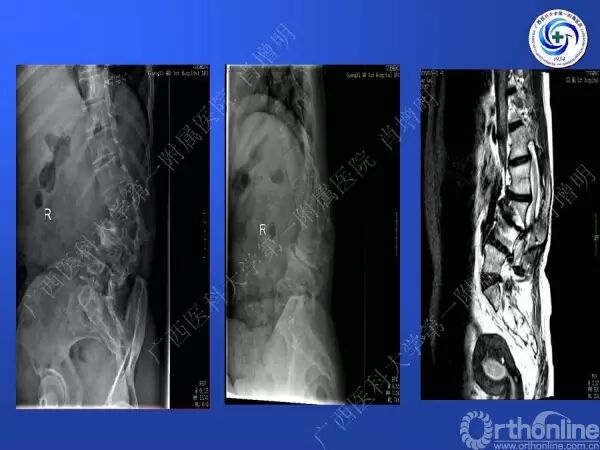

退变性脊柱侧凸是由于椎间盘退变后继发小关节退变,椎管和神经根管容积变化以及脊柱失稳,畸形等病理改变,以疼痛和神经压迫症状为主要表现的常见疾病。

退变性脊柱侧凸多发于50岁以上的中老年群体,是现代常见的老年疾病。多年来,针对该病的临床研究一直没有停步,广西医科大学第一附属医院肖增明教授细致地介绍了该病的诊疗进展。